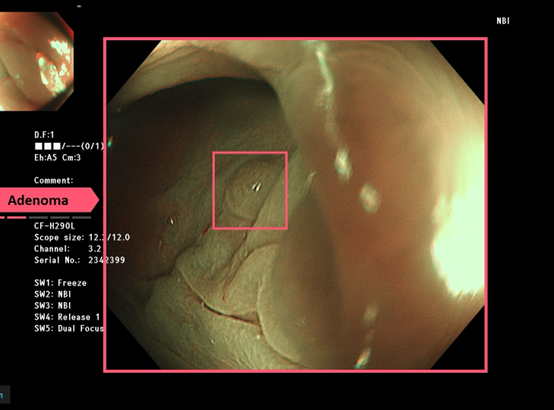

大腸鏡近年來整併了AI圖像辨識技術,可以第一時間透過電腦判讀,知道大腸癌的風險高低,大幅增加了大腸癌檢查的效率以及準確性。國外研究顯示施行大腸鏡時的腺瘤偵測率每提升1%,將可以降低鏡檢後發生大腸癌風險3% 之多,死亡率甚至可以降低5%。2022年國外研究顯示,藉AI人機協作進行大腸鏡檢查,約可提高14% ~ 30% 的腺瘤偵測率不等。

除了癌症判定,經由特殊光譜NBI、BLI以及放大效果,也可協助醫師立即 診斷瘜肉的好壞。簡單來說,就是讓 內視鏡 的訊號經過AI BOX即時處理,就能即時顯示於螢幕上,類似於醫師的第三隻眼睛,幫助揪出不易用肉眼檢視到的瘜肉。